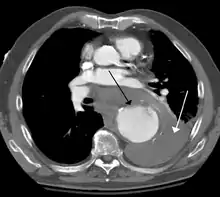

![]() أم دم الأبهر الصدري مع سهم يشير إلى الجانب الوحشي من شريان الأبهر. أم دم الأبهر الصدري مع سهم يشير إلى الجانب الوحشي من شريان الأبهر. | |